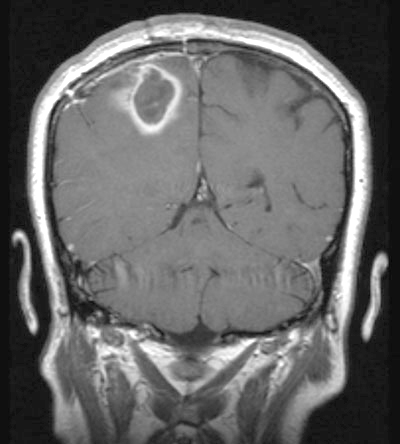

A 48-year-old woman presented to the emergency department (ED) with headache and left-sided weakness, initially diagnosed from a computed tomography (CT) scan as a right parietal stroke. Magnetic resonance imaging (MRI) showed a parietal mass consistent with a tumour (Box 1, A). Using stereotactic craniotomy, purulent material was drained from the lesion, and S. milleri and Actinobacillus actinomycetemcomitans were grown on culture.

After 8 weeks’ treatment with intravenous benzylpenicillin, ceftriaxone and metronidazole, the woman’s neurological deficits resolved and an MRI scan showed scar tissue in the right parietal lobe without reaccumulation of pus.